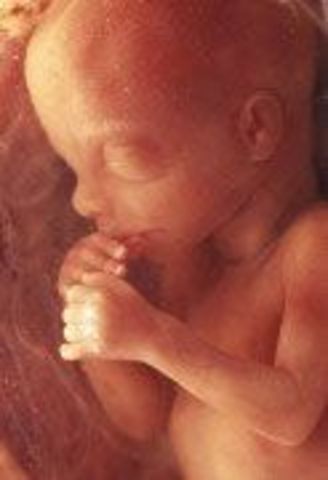

• week 20

week 20

Your baby weighs about 10 1/2 ounces now. He's also around 6 1/2 inches long from head to bottom and about 10 inches from head to heel — the length of a banana. (For the first 20 weeks, when a baby's legs are curled up against his torso and hard to measure, measurements are taken from the top of his head to his bottom — the "crown to rump" measurement. After 20 weeks, he's measured from head to toe.)